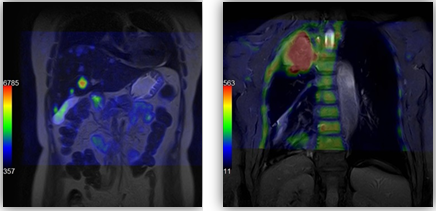

Онкологія